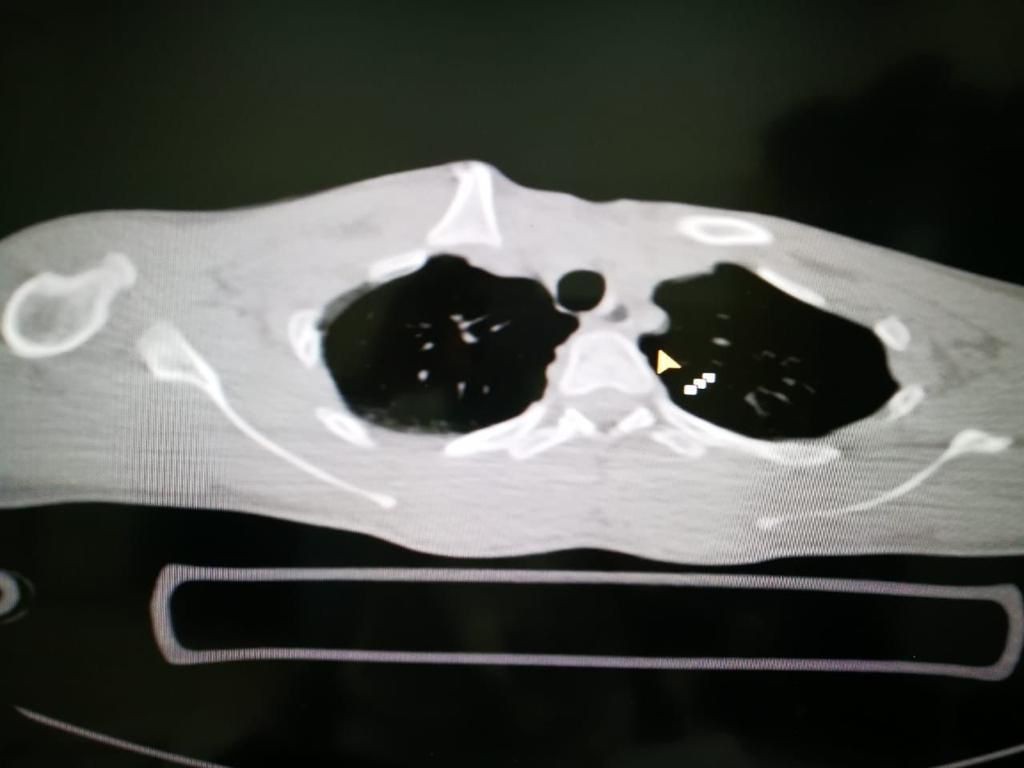

تمكن فريق طبي في منطقة تبوك من إجراء عملية دقيقة ومعقدة لإرجاع عظم الترقوة والقفص الصدري إلى مريض تعرض لحادث مروري إستغرقت مدتها 4 ساعات تكللت ولله الحمد بالنجاح. وقالت صحة تبوك إن أطباء مستشفى الملك خالد في منطقة تبوك تمكنوا ولله الحمد من إنقاذ حياة شاب وصل لقسم الإسعاف بحالة حرجة نتيجة تعرضه لحادث مروري فقد بسببه كميات كبيرة من الدم جراء النزيف الذي فقده الجسم ، وتم تقديم الإسعافات الطبية الأولية العاجلة لإيقاف النزيف. وأكدت أنه بعد إجراء الفحوصات السريرية والإشعاعية والمخبرية تبين وجود انفصال تام لعظم الترقوة مع عظم القفص الصدري بالإضافة إلى كدمات في الرئة وكسور في عظام الحوض وخلع في المفصل مما استدعى دخوله بشكل عاجل لغرفة العمليات الكبرى وإجراء عملية أمامية على الصدر شملت المفصل القصي الترقوي وعظم الترقوة اليمنى مترادفات وإزالة الضغط على القسم العلوي من الرئة والشريان والأوردة والأعصاب التي تغذي الطرف العلوي وتفريغ التجمع الدموي الناتج عن الخلع والكسر وإعادة الجزء المكسور من الترقوة من داخل القصي والربط بين الضلع الأيمن الأول والترقوة للمحافظة على ثبات المفصل، حتى استقرت الحالة لتنقل بعدها إلى غرف التنويم لاستكمال المتابعة الطبية لها حتى الخروج من المستشفى- بإذن الله- بصحة جيدة. يذكر أن مستشفى الملك خالد خلال ال (3) الأشهر الماضية أجرى أكثر من 1031 عملية منها 381 عملية طارئة و 650 عملية روتينية.